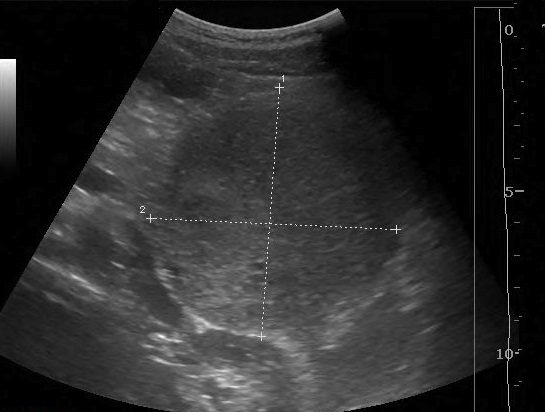

Image TDM d'une

tumeur

pseudo-papillaires et solides du queue du pancreas

avec aspect lesionnel de masse hypodensite ,nonhomogene

mixte de contenue solide et kystique , a bord bien

limite , encapsule . Image radiologique TDM non de

contrast intraveineuse , coupe axiale |

|

Meme cas apres injection de

contrast intraveineuse , phase veineuse . Image de

contenue solide et kystique retrouvent bien et plus de

nette . Image calcifie de la parois et des septales peut en

s'observer |